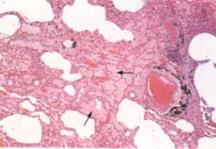

麴黴球其他輔助檢查:X線上麴黴球表現為肺空洞或胸膜腔內圓形緻密陰影,其邊緣有透光暈影。若空腔較大,尚可見球形陰影有蒂與洞壁相連,形如鐘擺,球形陰影可隨體位變化而改變形態。如果空洞較小,球形病灶填充了大部分空腔,其暈影很小,僅呈一狹長的半月形透亮帶。有學者曾在2例X線平片、體層片和支氣管造影片均無陽性發現的隱源性大咯血患者套用支氣管動脈造影定位後行手術治療,病理髮現1cm左右的細小支氣管囊腫繼發麴黴球。胸部CT檢查特別是高分辨CT的套用為發現細小麴黴球和鑑別診斷提供了有用技術。